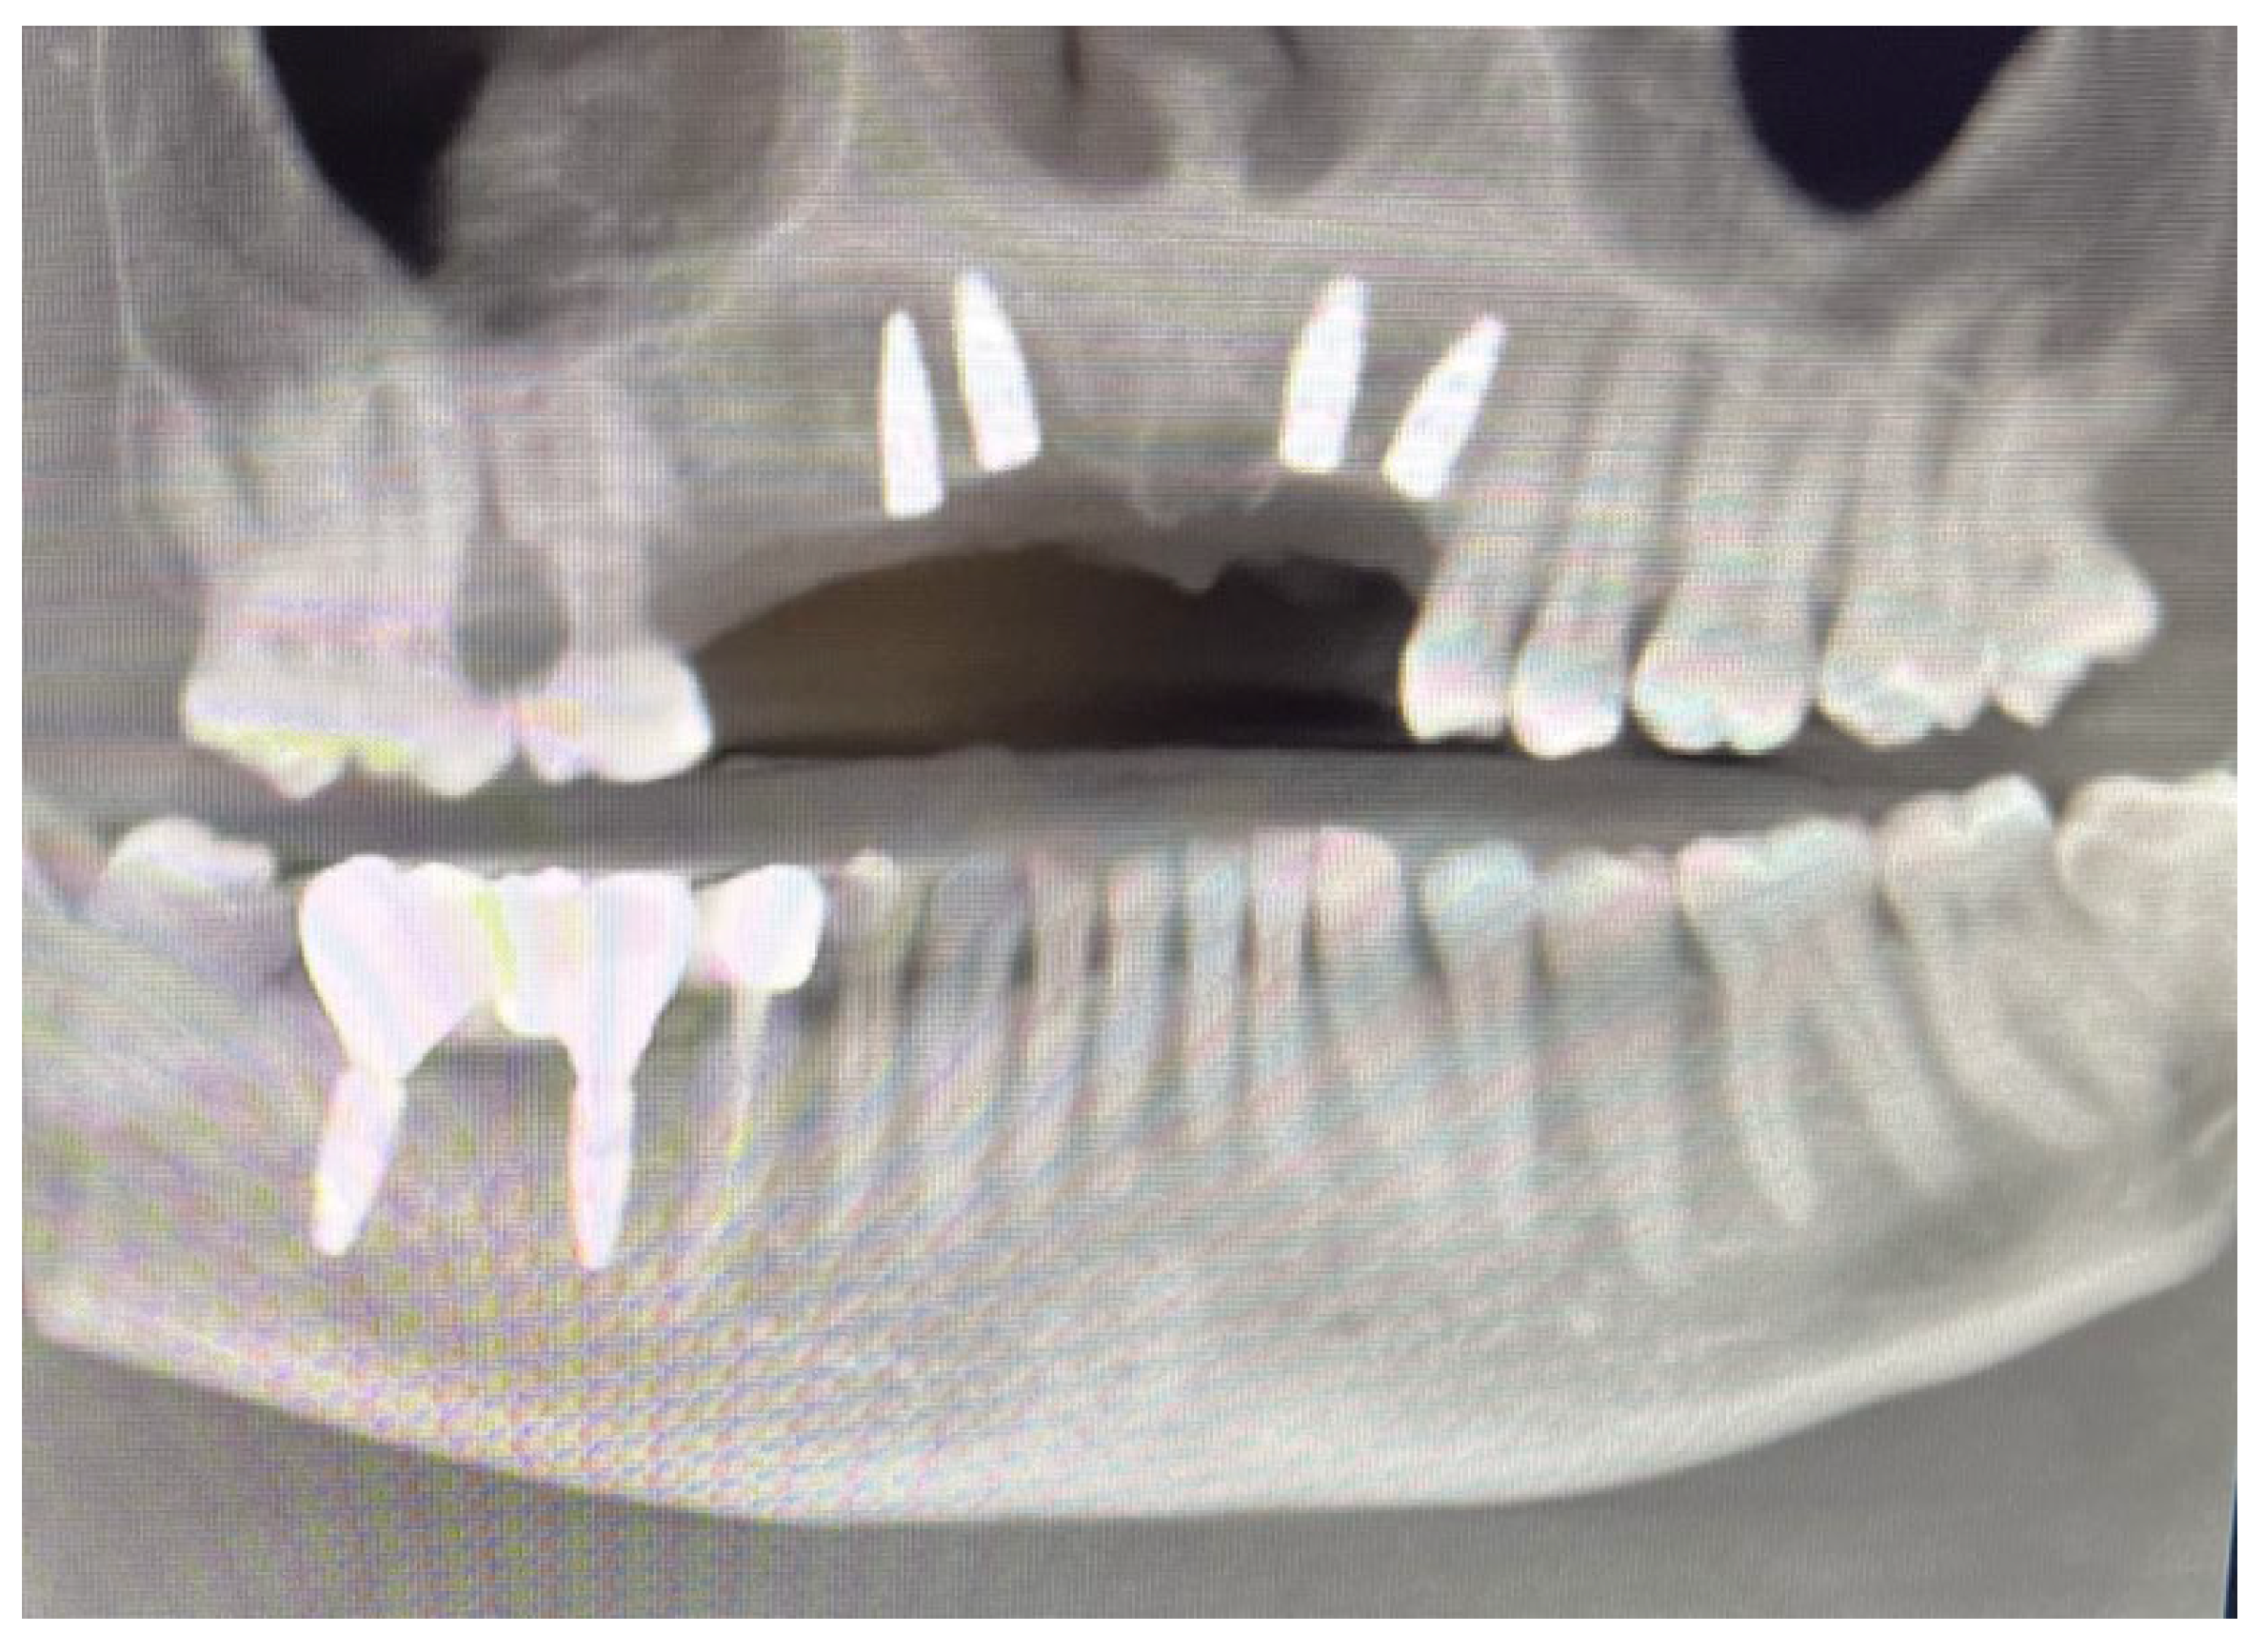

60 days after the extraction of the upper front teeth, it was discovered that the upper right premolars were also affected by significant root resorption, as well as 46 and 47 (Figure 6).

Figure 6. Evolution of the external resorptions in 46-47.